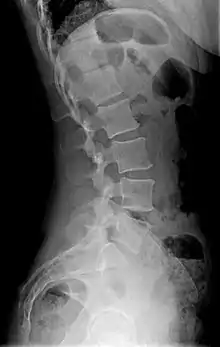

X-ray

Precise diagnosis is done by looking at a complete medical history, physical examination, and other tests of the patient. X-rays are used to measure the lumbar curvature. On a lateral X-ray, a normal range of the lordotic curvature of between 20° and 60° has been proposed by Stagnara et al., as measured from the inferior endplate of T12 to the inferior endplate of L5.[18] The Scoliosis Research Society has proposed a range of 40° and 60° as measured between the upper endplate of Th12 and the upper endplate of S1.[18] Individual studies, although using other reference points, have found normal ranges up to approximately 85°.[18] It is generally more pronounced in females.[18] It is relatively constant through adolescence and young adulthood, but decreases in the elderly.[18]